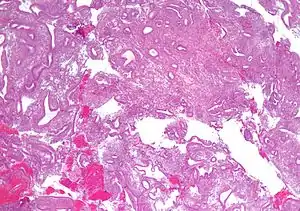

| Micrograph showing simple endometrial hyperplasia, where the gland-to-stroma ratio is preserved but the glands have an irregular shape and/or are dilated. Endometrial biopsy. H&E stain. | |

Like other hyperplastic disorders, endometrial hyperplasia initially represents a physiological response of endometrial tissue to the growth-promoting actions of estrogen. However, the gland-forming cells of a hyperplastic endometrium may also undergo changes over time which predispose them to cancerous transformation. Several histopathology subtypes of endometrial hyperplasia are recognisable to the pathologist, with different therapeutic and prognostic implications.[3]

- Endometrial hyperplasia (simple or complex) - Irregularity and cystic expansion of glands (simple) or crowding and budding of glands (complex) without worrisome changes in the appearance of individual gland cells. In one study, 1.6% of patients diagnosed with these abnormalities eventually developed endometrial cancer.[6]

- Atypical endometrial hyperplasia (simple or complex) - Simple or complex architectural changes, with worrisome (atypical) changes in gland cells, including cell stratification, tufting, loss of nuclear polarity, enlarged nuclei, and an increase in mitotic activity. These changes are similar to those seen in true cancer cells, but atypical hyperplasia does not show invasion into the connective tissues, the defining characteristic of cancer. The previously mentioned study found that 22% of patients with atypical hyperplasia eventually developed cancer.[6]